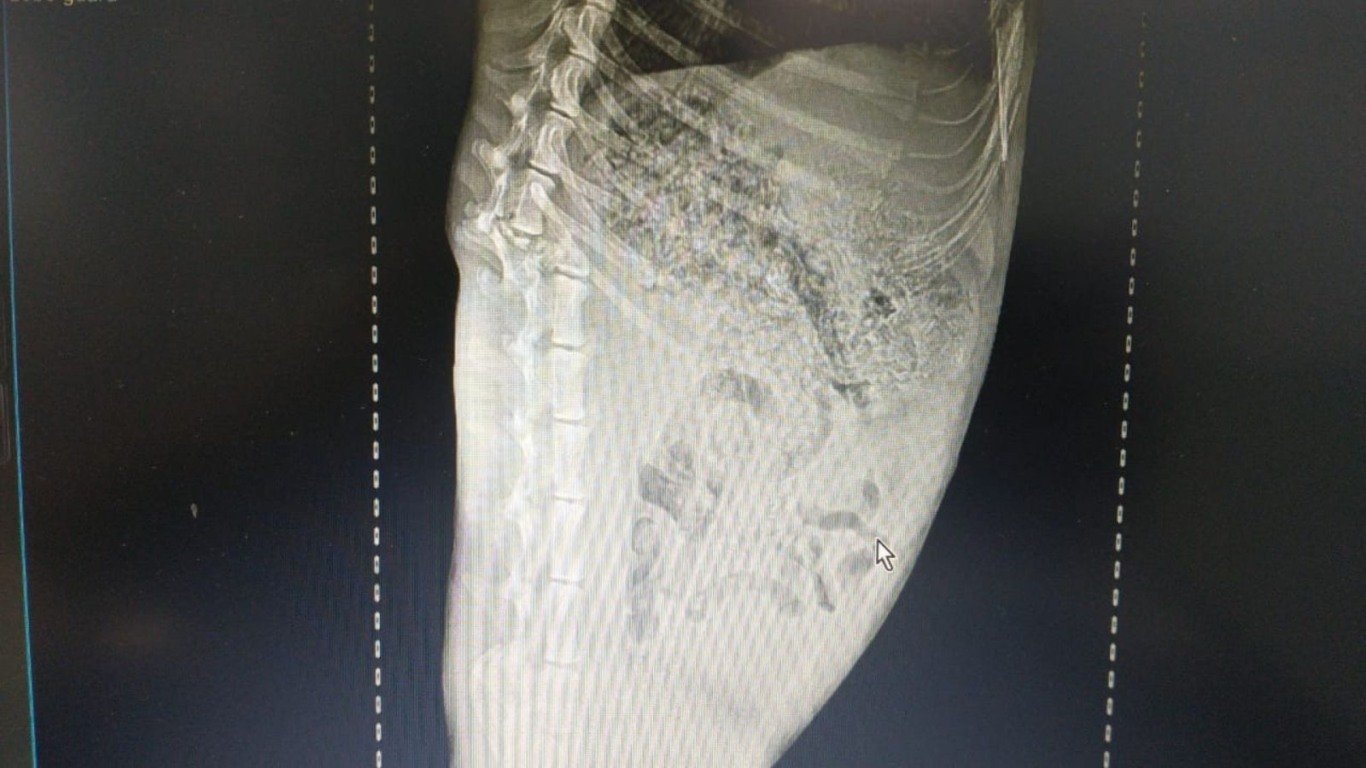

A equipe precisou anestesiar o lobo para realizar o manejo de forma adequada. Em seguida, o também o trouxeram até o Cras, onde exames radiográficos constataram fratura completa na coluna. De acordo com a Mata, o animal está com quadro de saúde muito crítico, mas a equipe empreende todos os esforços para a sua recuperação.